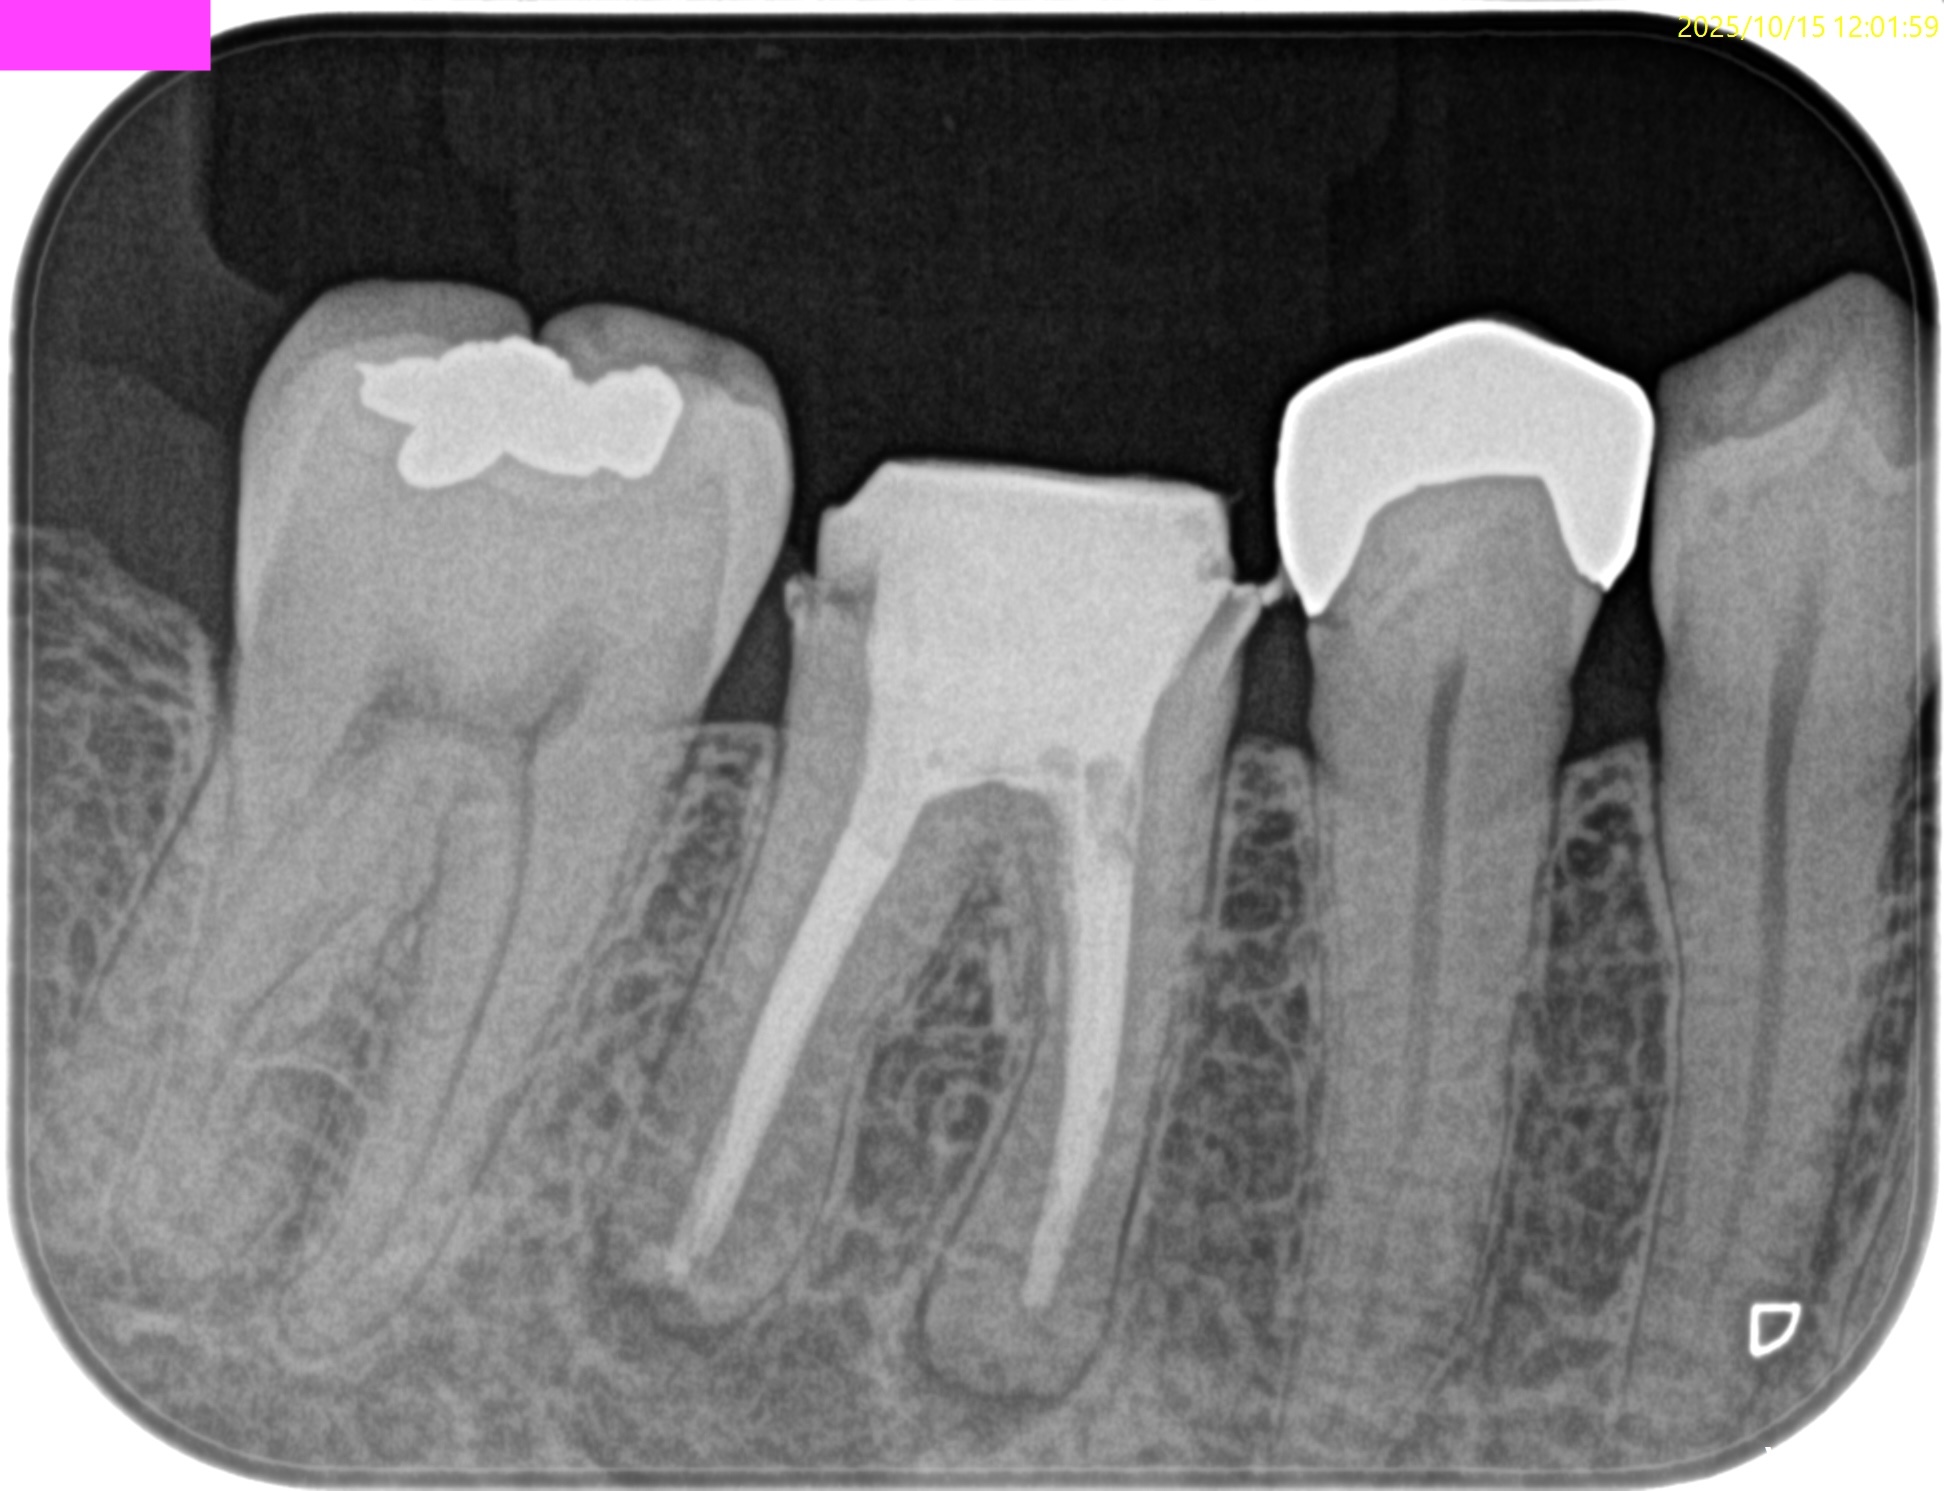

#30 Re-RCT(2025.10.15)

全ての根管は閉鎖していた。

術後にPA, CBCTを撮影した。

MB

ML

D

B